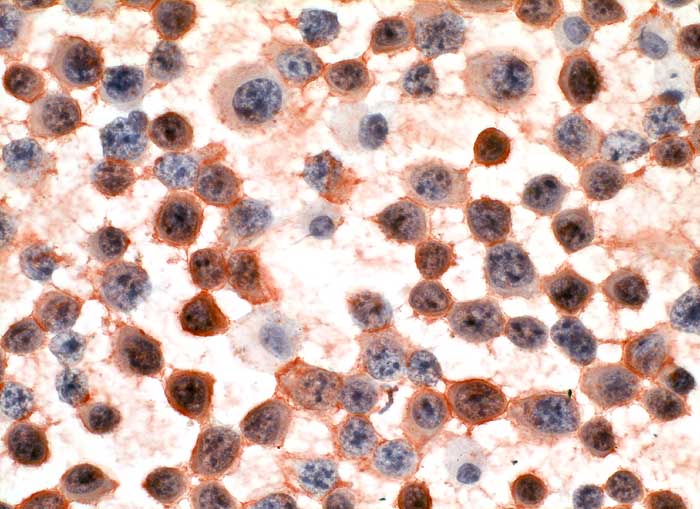

CD138

Anfärbung:

Zellmembran

Reaktion im Normalgewebe:

Plasmazellen sind positiv.

Reaktion in Neoplasien:

Neoplastische Plasmazellen reagieren positiv.

Diagnostischer Nutzen:

Diagnose des multiplen Myeloms. Identifikation von Plasmazellen.